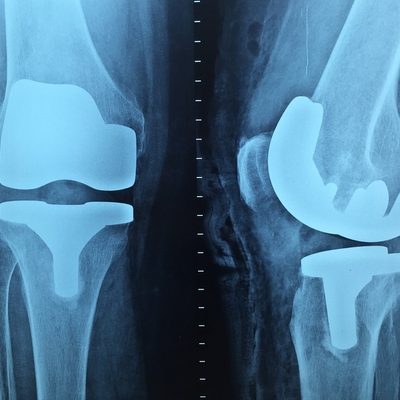

Click on an image below to view more info.